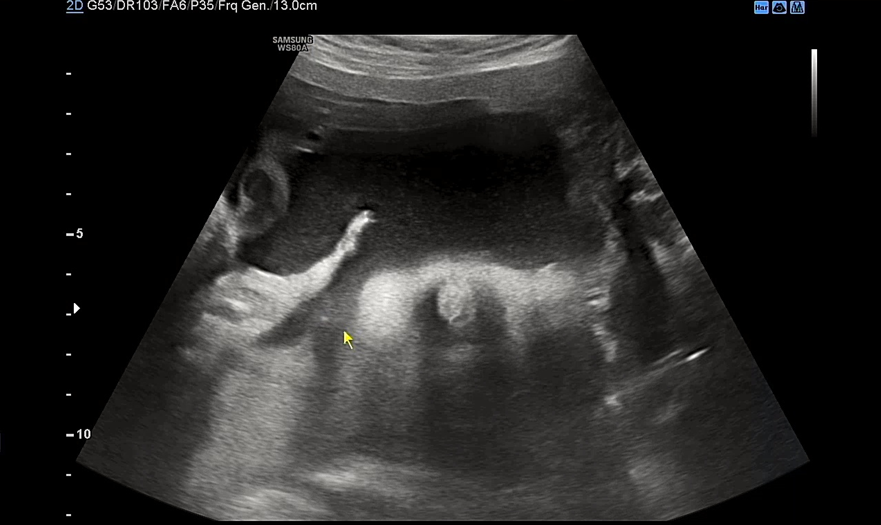

이 날 우리 아기는 배에 얼굴을 파묻고선 얼굴을 보여주지 않았다. 아니 지난주에는 그렇게 잘 보여주더니 이번엔 얼굴을 돌릴 기미가 1도 안보였다. 요건 얼굴을 돌린 상태에서 귀만 살짝 보여준 모습.

눈이 살짝살짝 보이다가도 푹 다시 파묻어버리는. 다음 검사때에는 초코우유를 먹여야겠다며 남편이 어찌나 아쉬워하던지 모르겠다. 초음파 검사를 마치면 항상 원장님께서 궁금한 거 없냐고 여쭤보시는데 다른 임산부들은 뭘 물어볼까? 이제 운동을 조금 늘려도 되냐고 여쭤봤는데 무리되지 않는 선에선 괜찮다고 하셨다. 아주 막달이 아니고선 운동은 크게 권장되지 않는 느낌이다. 아기도 너무 잘 자라고 있고 내 컨디션도 너무 좋아 별로 물어볼 게 없었다. 사실 이 날 백일해 주사를 접종하기로 했는데 백신이 떨어져서 접종을 하지 못했다. 34주 전까지는 접종이 권장되는데 원장님께서 소아과나 정형외과에 물량이 있을 수 있으니 가까운 곳으로 전화를 해보라고 하셨다. 일단 2주 뒤 진료라서 그때 병원을 와보고 백일해 주사가 또 없으면 가까운 병원에 전화를 돌려보기로 했다. 이제 30주가 되니 출산용품 리스트에서 남은 물건들도 모조리 다 구입하고 빨래도 시작해야 한다. 엄청 일찍부터 이것저것 알아보고 준비한 거 같은데 한도 끝도 없는 출산 준비. 시간이 점점 부족한 기분이다.